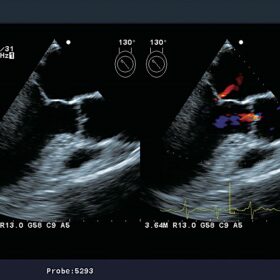

Cardiovascular

- eTRACKING (Echo Tracking)

- Arterial Stiffness

- Flow Mediated Dilatation (FMD)

- Wave Intensity (WI)

- Automated Intima-media Thickness (IMT) Measurement

- CW Doppler by the Linear Probe

- Transit Time of Vessel Flow (TVF)

- Automated Segmental Motion Analysis (A-SMA)

- Stress Echo

- TDI (Tissue Doppler Imaging) Analysis

- Free Angular M-mode (FAM)

- Asynchrony Measurement

- Patient Friendly Trans-esophageal Probes

Aloka UST-5293-5 TEE Cardio

Aloka UST-52119S TEE Cardio